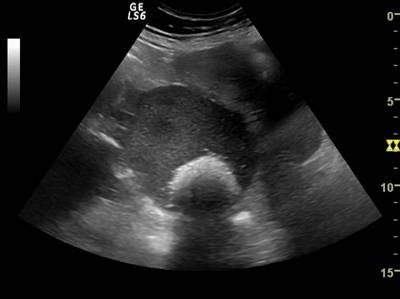

Fig. nr.387. Formatiune anecogena uniloculara cu perete subtire ( sageata ), fara lichid in Douglas ( chist functional , la o pacienta de 15 ani , la ecografia abdominala

Fig. nr.388. Chist ovarian anecogen , unilocular , cu perete subtire la ecografia transvaginala